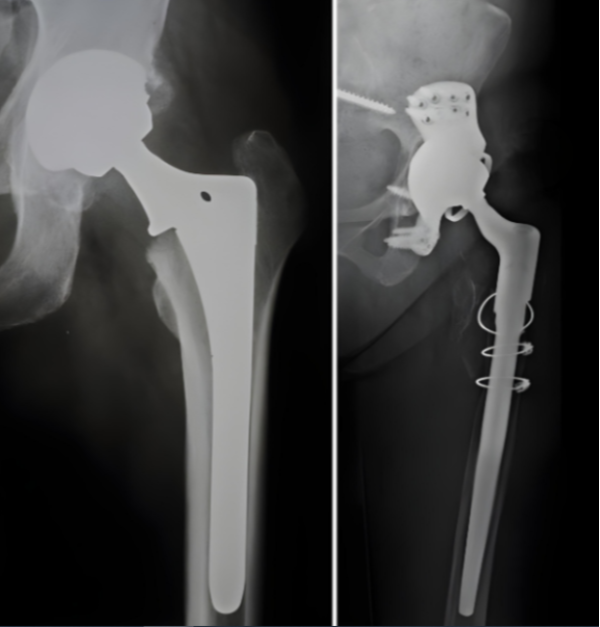

Revision Hip Replacement in Bangalore – Restoring Function and Comfort